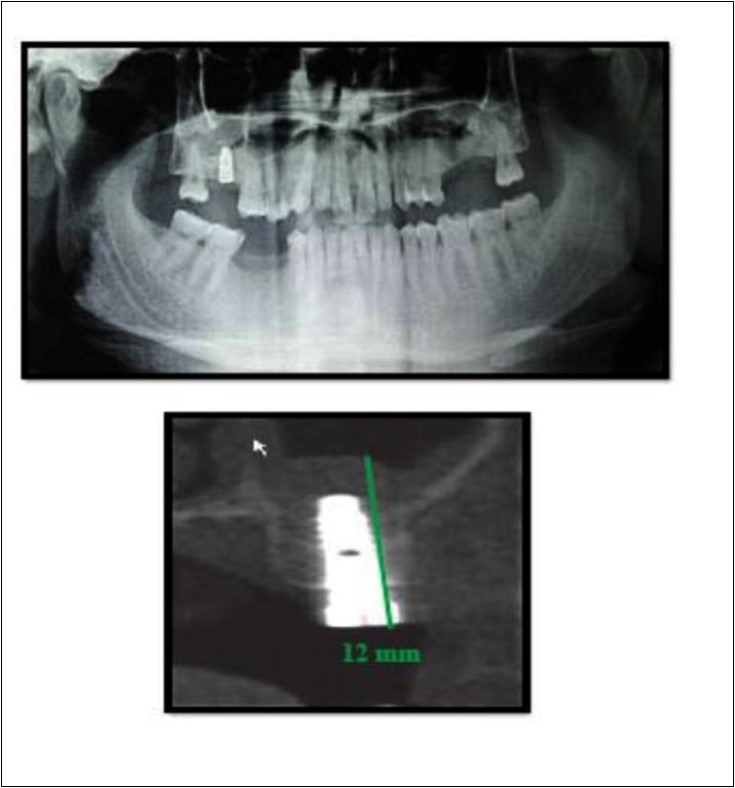

A 75 year old man reported to the unit seeking options for replacement of his missing upper right first molar with fixed prosthesis. Due to the residual bone height of 5.3 mm, the patient was advised and subsequently, underwent the procedure of indirect sinus elevation using sinus osteotomy in relation to 16 region followed by placement of a dental implant measuring 5 mm x 10 mm under local anesthesia and strict aseptic protocols. The implant was allowed to osseo-integrate for a period of six months during which the patient was followed periodically. At the end of 6 months, a CBCT scan showed an increase in bone height to 11.5 mm. (Figure 5)

Figure 5.Pre-operative and post-operative Orthopantomographs and cross sections of CBCT showing residual alveolar bone height

Case Report 4

A 19 year old young woman was referred to Department seeking options for rehabilitation of missing right upper first molar with fixed prosthesis as she was uncomfortable with the removable partial denture in relation to 16. The residual bone height in region was 4 mm in 16 tooth region. Patient was taken-up for direct sinus elevation via lateral window approach for sinus augmentation in relation to 16. Under aseptic conditions and local anesthesia, lateral wall of maxilla was exposed after muco-periosteal flap elevation. A window was created of 1cm diameter corresponding to apical aspect of 16. Sinus membrane was identified and elevated using sinus elevators and reamers without perforating the lining. Once the sinus membrane was elevated, graft material was dispensed to achieve an augmentation of 1cm assessed clinically and confirmed using post-operative OPG. At the end of 6 months, a CBCT scan showed an increased bone height of 12.7 mm. (Figure 6)

Figure 6.Pre-operative and post-operative Orthopantomographs and cross sections of CBCT showing residual alveolar bone height